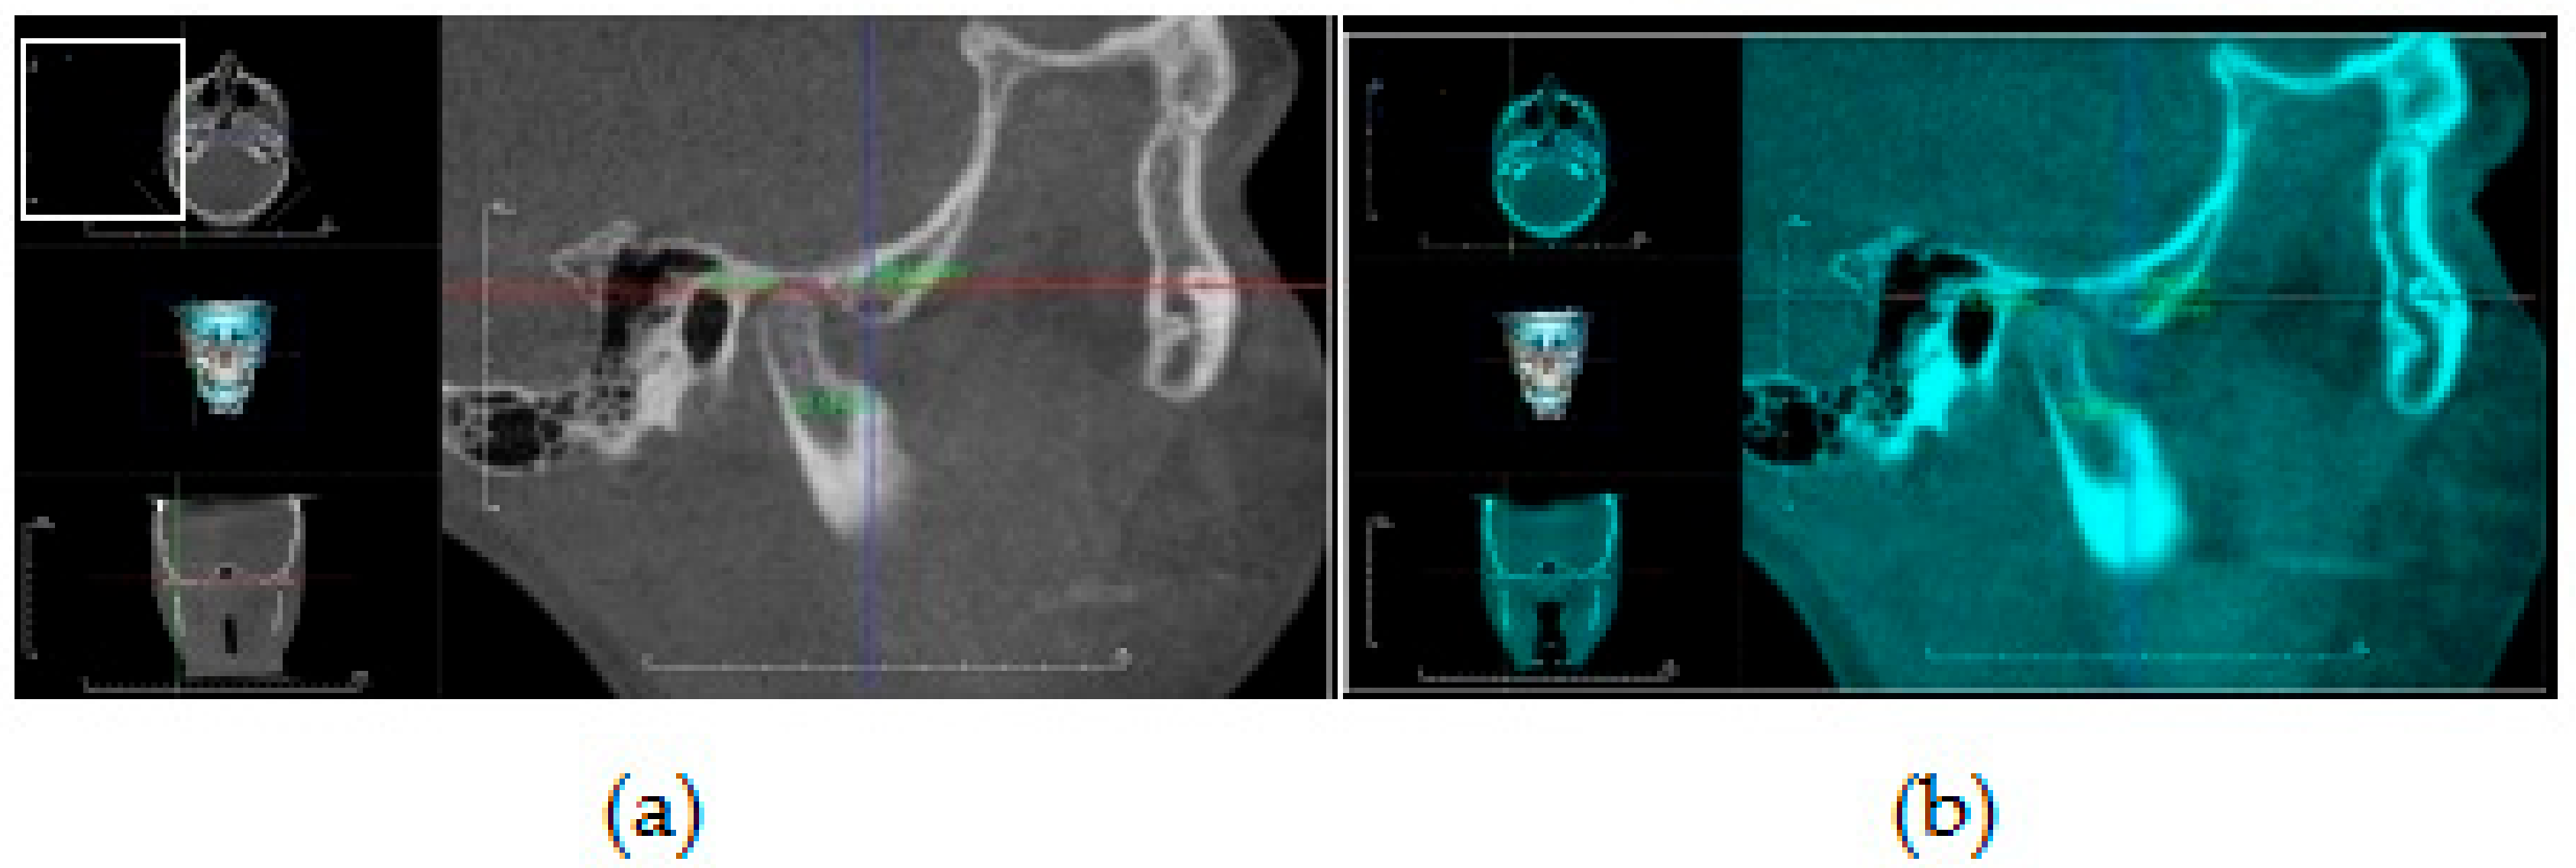

Assessment of condylar head volume: Both T1 and T2 mandibular 3D CBCT images were segmented for superimposition and condylar volumetric measurements via special software (Mimics software v. 16.0, Materialise NV, Leuven, Belgium). The assessment method was in accordance with the previous studies by Bayram et al. [17] and Yildirim et al. [16]. This was performed by the “superimposition” function module of the software, which was a rigid body registration in accordance with landmark fitting. Foramen mentale, superior and posterior points of antegonial notches were used on both the right and left sides (Figure 2). Next, the custom planar osteotomy function of the software was used to establish a plane of 0.1 mm passing tangentially to the distal slope of the coronoid process, thereby separating the condyles of superimposed images (Figure 3). Subsequently, after segmenting the superimposed condylar images, condylar volumetric measurements were automatically calculated in mm3. The same process was employed for both right and left condyles in each patient.

Figure 3. CBCT mandibular 3D images showing construction of plane passing tangent to distal slope of coronoid process to slice right and left condyles of superimposed images using Mimics software.